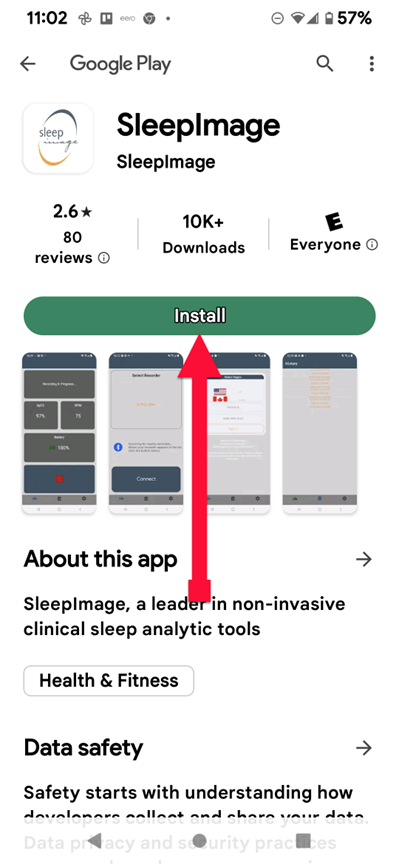

SLEEPIMAGE APP (Android)

SLEEPIMAGE APP (Android)

SLEEPIMAGE APP (Android)

SLEEPIMAGE APP (Android)

SLEEPIMAGE APP (Android)

SLEEPIMAGE APP (Android)

SLEEPIMAGE APP (Android)

SLEEPIMAGE APP (Android)

SLEEPIMAGE APP (Android)

SLEEPIMAGE APP (Android)

SLEEPIMAGE APP (Android)

SLEEPIMAGE APP (Android)

SLEEPIMAGE APP (Android)

SLEEPIMAGE APP (Android)

SLEEPIMAGE APP (Android)

SLEEPIMAGE APP (Android)

SLEEPIMAGE APP (Android)

SLEEPIMAGE APP (Android)

SLEEPIMAGE APP (Android)

SLEEPIMAGE APP (Android)

SLEEPIMAGE APP (iPhone)

SLEEPIMAGE APP (Android)

SLEEPIMAGE APP (Android)

SLEEPIMAGE APP (Android)

SLEEPIMAGE APP (Android)

SLEEPIMAGE APP (Android)

SLEEPIMAGE APP (Android)

SLEEPIMAGE APP (Android)

SLEEPIMAGE APP (Android)